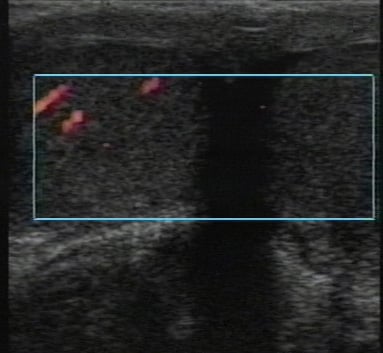

- Color Doppler or power Doppler may be helpful to identify flow patterns in the acutely tender testicle. (Figure 5) When blood flow is absent in the affected testicle, the diagnosis of testicular torsion is clear. Occasionally decreased blood flow seen in early torsion can be erroneously diagnosed as normal. Thus, comparison to the contralateral side is crucial.

Figure 5. Transverse plane through both testes. The power Doppler image of the scrotum demonstrates right testicular perfusion. The swollen left testicle is not perfused. (Image courtesy of Michael Blaivas, MD)